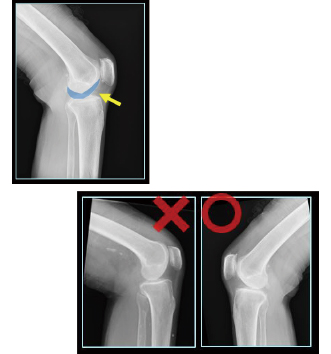

画像診断ワークステーション「CS-7ポジショニング判定支援機能」

被ばく線量管理「FINO.XManage」一般撮影業務管理システム「RADInsite」

『FINO.XManage』は各種モダリティやPACSから線量情報を取得し画像と共に管理可能なシステムです。画質を担保しながら医療被ばくの最適化に貢献します。更に一般撮影の多様なデータを可視化し分析可能なマネジメント機能『RADInsight』を搭載。再撮影の管理に加え撮影技術の教育支援ツールも備えています。『FINO.XManage』は医療被ばくの最適化に向けてお客様をサポートします。